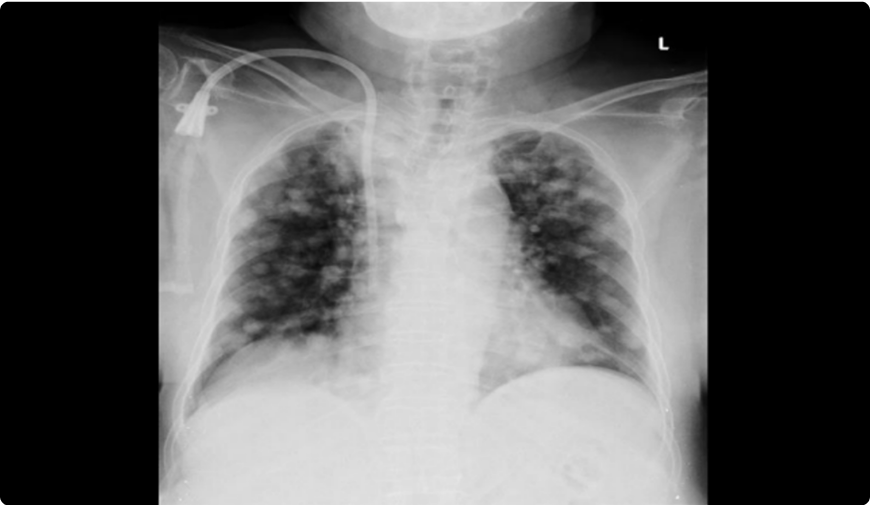

半年後の定期健診(2006年6月)で腫瘍マーカーのCEAが断続的に上昇していたので、レントゲンを撮影した結果、肺癌と診断された。

肺癌と診断された後、2006年7月に緊急手術が行われ、胸を開いてみると、レントゲンで見つかった2センチメートルの2個の腫瘍のほかに、左肺葉と胸膜に転移が見つかり、なすすべがありませんでした。

その後T様は一年半、分子標的治療等を受け、癌をコントロールしていました。しかし、腫瘍マーカーのCEAの動きは激しく、癌の安定化には至りませんでした。そこで2008年にT様の友人である医師の紹介でアントロキノノール含有エキスの摂取を始めました。

T様はアントロキノノール含有エキスを服用し続け、毎月定期健診をしていたところ、病状は改善されていきました。そして一年後の2009年7月24日の各種検査でがん細胞は検出されなくなり、他の検査の数値も安定していました。